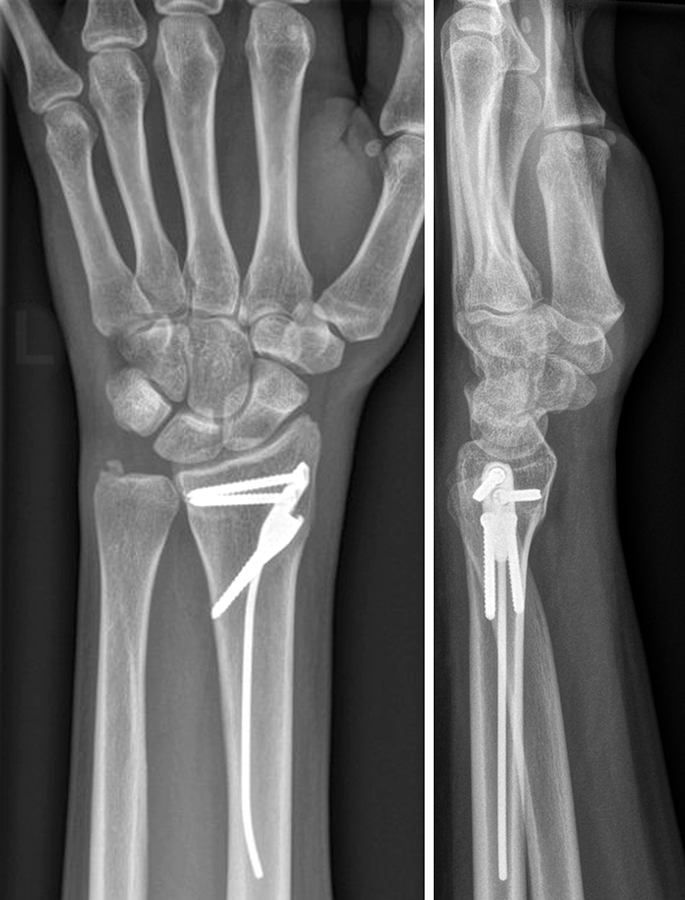

Finding an industrial partner for the AO-approved DRIM-Nail is ongoing (as of November 2022). The nail is 7.0 mm in diameter and single packed as a 'one size fits all' sterile implant. The nail itself is made from titanium and the additional 2.5 mm diameter screws for fixation (ranging from 14−36 mm) are made of stainless steel (Fig 3). The instrument set is lean but comprehensive and intuitive to use. All instruments are nonsterile and validated according to 41medical reprocessing.

The patient was a 25-year-old woman who sustained a displaced, unstable extraarticular fracture of the left distal radius while snowboarding.

After closed reduction a dorsal re-dislocation of 25° occurred (Fig 4a). There are additional apparent signs of instability: dorsal comminution (Fig 4a) and fracture of the ulnar styloid (Fig 4b). Therefore, a considerable potential for further dislocation is present which is likely to occur in a cast. This young, active, and demanding patient wishes to return to her activities as early as possible. This can only be achieved with an operative fracture fixation. The nail was chosen instead of a plate. This allowed an almost instant functional use of her hand, which allowed her to return to work at 2 weeks postoperatively without additional fixation or a splint and full unprotected function of her wrist at 6 weeks.